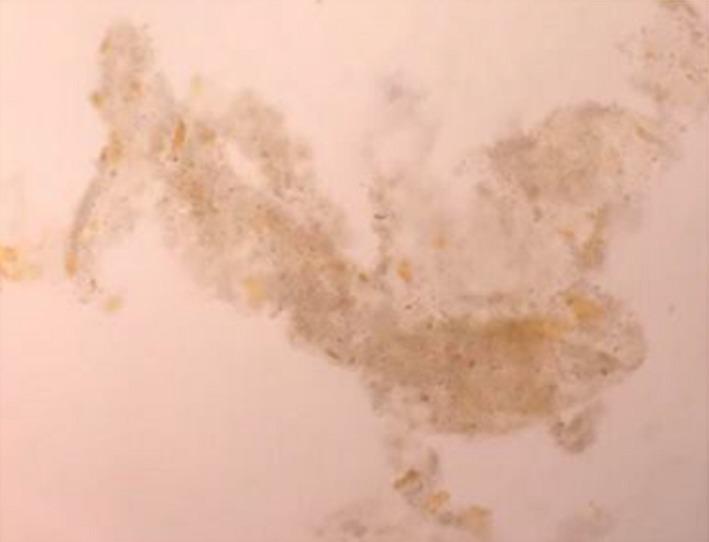

Bile cast nephropathy is characterized by the presence of bile casts associated with renal failure and/or proximal tubulopathy in cases of severe hyperbilirubinemia. The clinician should carefully examine the urine samples for characteristic bile-stained granular casts in suspected case.

胆汁管型肾病的特征是在严重高胆红素血症病例中出现与肾衰竭和/或近端肾小管病变相关的胆汁管型。临床医生在疑似病例中应仔细检查尿液样本,寻找特征性的胆汁染色颗粒管型。